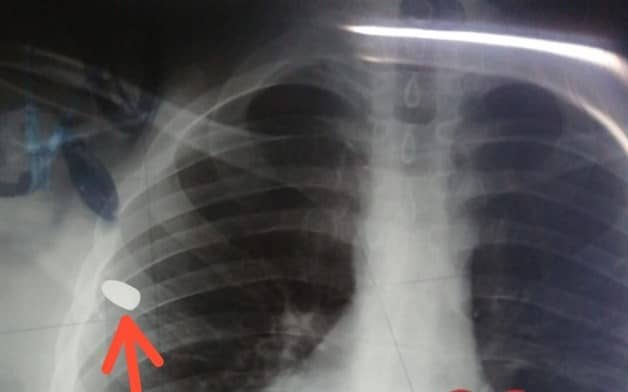

También se reportó el ingreso de dos masculinos heridos por bala a la base de Cruz Roja del Leyva Solana, se dice que uno de ellos tenía un proyectil en una de sus costillas.